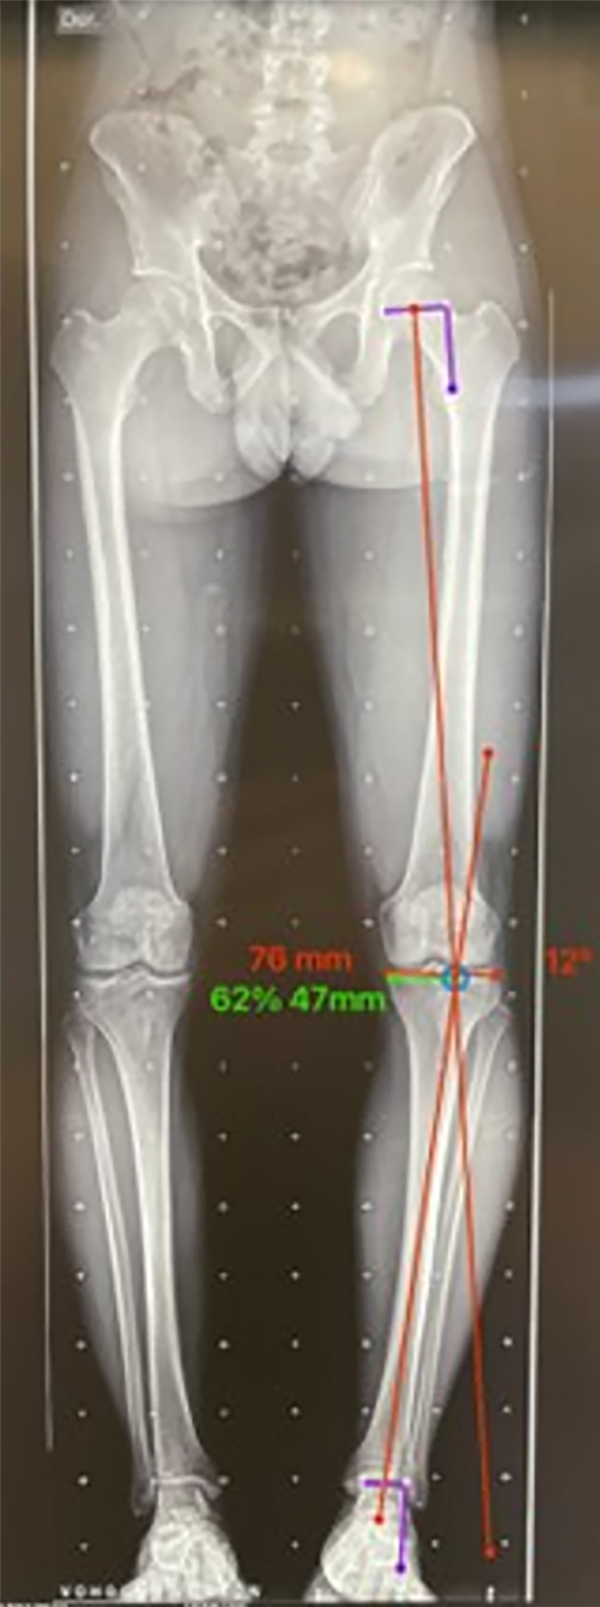

Una vez determinado esto, se traza una línea desde el centro de la cabeza femoral hasta el punto determinado en los platillos tibiales y una segunda línea desde el centro del tobillo hasta el punto determinado de la corrección. El ángulo formado por estas dos líneas corresponde al ángulo de corrección de la línea de carga7 (figs. 8 y 9).

Figura 8: Cálculo del punto de corrección de la deformidad en paciente con artrosis: la longitud total del ancho de los platillos tibiales es 76 mm y el 62% desde medial a lateral es 47 mm, a donde va a ir la corrección y el ángulo a corregir es de 12°.

Figura 9: Cálculo del punto de corrección de la deformidad en paciente sin artrosis: se calcula al 50% para evidenciar el cambio, encontrando que la mitad es 38 mm y el ángulo de corrección disminuye a 9°. Este cambio de la indicación de la osteotomía hace que en la figura 8 amerite una doble osteotomía (DLO) y en esta sólo con osteotomía de tibia pueda ser corregida la deformidad.